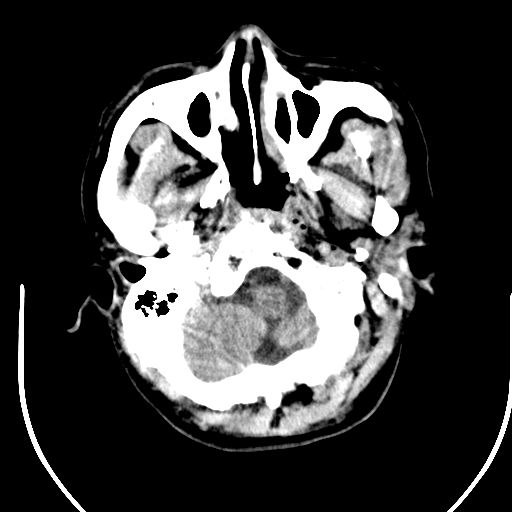

标题: CT25423:头部外伤意外发现右顶叶??? [打印本页]

标题: CT25423:头部外伤意外发现右顶叶???

ct值约13hu。